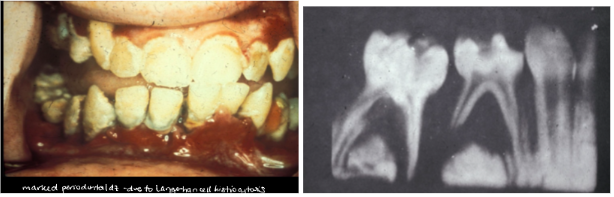

*Lesions: sore mouth, gingival ulcers, halitosis, gingivitis, loose teeth and premature loss, loss of alveolar bone - Mimics advanced periodontal disease

Hand-Schuller-Christian disease treatment

*Premature periodontal disease

*Severe periodontal bone loss

*Tooth mobility

*Marked gingival recession